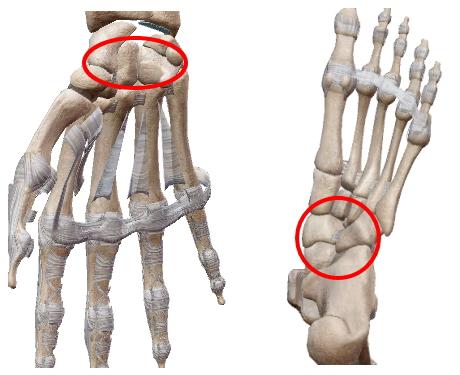

| 球関節の楕円バージョン。楕円なので回旋は出来ない2軸の関節。環椎後頭関節、橈骨手根関節、中手指節関節(母指以外)。 |

| 馬の鞍(くら)を上下に重ねたような形から鞍関節(あんかんせつ)。楕円関節同様回旋は出来ない2軸の関節。母指の手根中指節関節。 |

平面関節

| 平面に近い関節面が滑るように動く多軸関節。関節面が小さいので可動範囲は極めて小さい。 椎間関節、仙腸関節、肩鎖関節、脛腓関節、手根間関節、足根間関節、豆状骨関節。 *仙腸関節、脛腓関節は、関節面の半分が線維性軟骨結合が占め関節腔が非常に小さいので『半関節』とも。 |